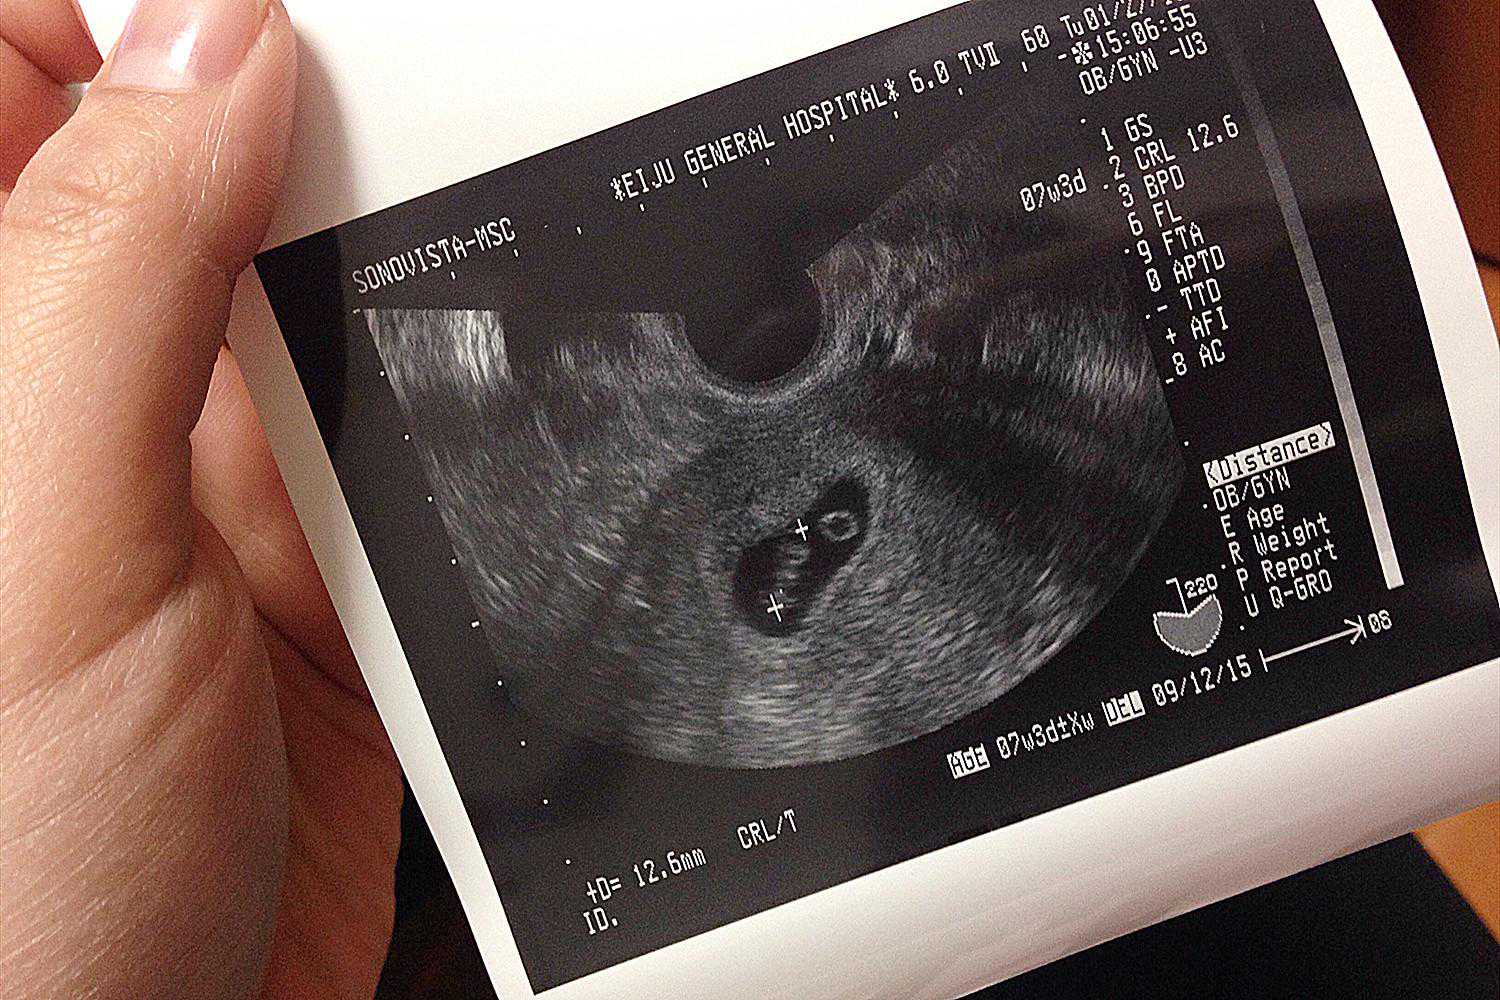

在得知自己怀孕后,准妈妈们第一项应该检查的就是孕酮和HCG,排除所有不利的可能性,如果孕酮和HCG翻倍情况不是很理想,也可以尽早的采取措施。